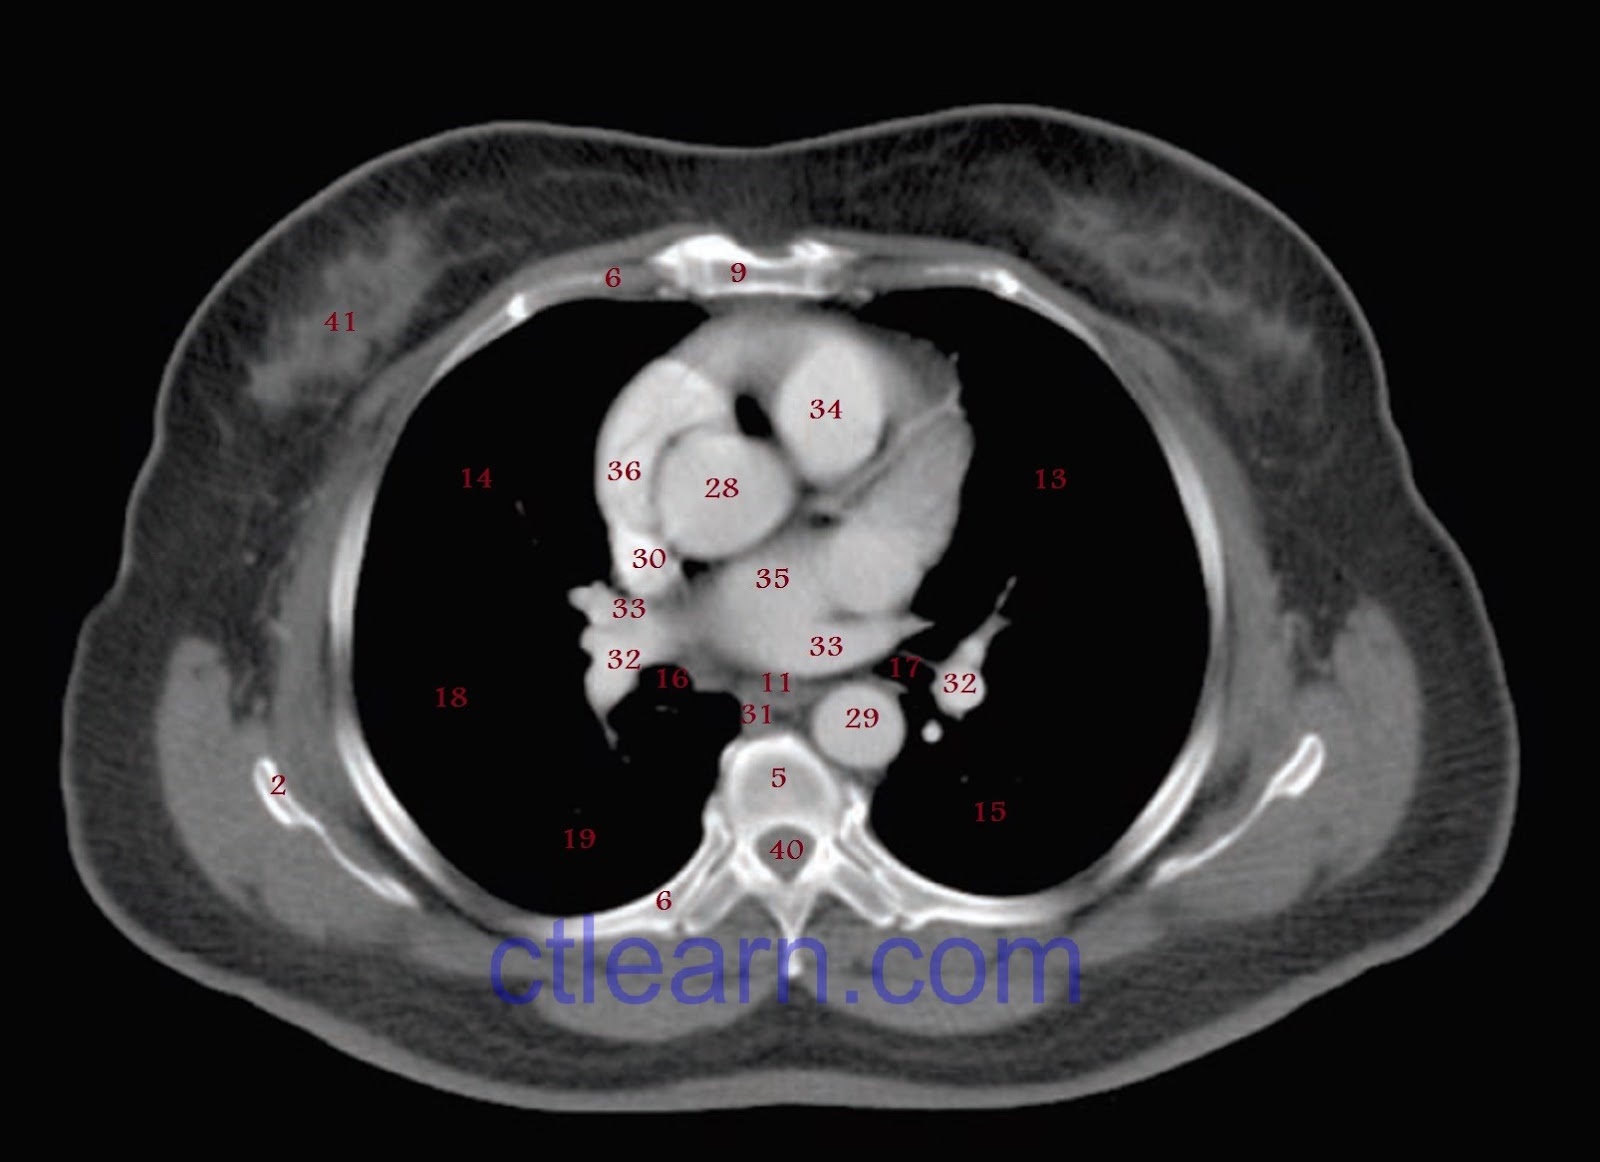

From www.ctlearn.com

Learn CT Scan Anatomy CT Axial Chest Ct Scan Labeled Computed tomography (ct) scans are an extremely common imaging modality. Annotated teaching ct head in standard and bone windows. This article will explain how to read an abdominal ct scan on the concrete examples of the ct images of the abdomen. It is performed with a higher radiation dose and larger dose of iv contrast, which. In this article, we. Ct Scan Labeled.